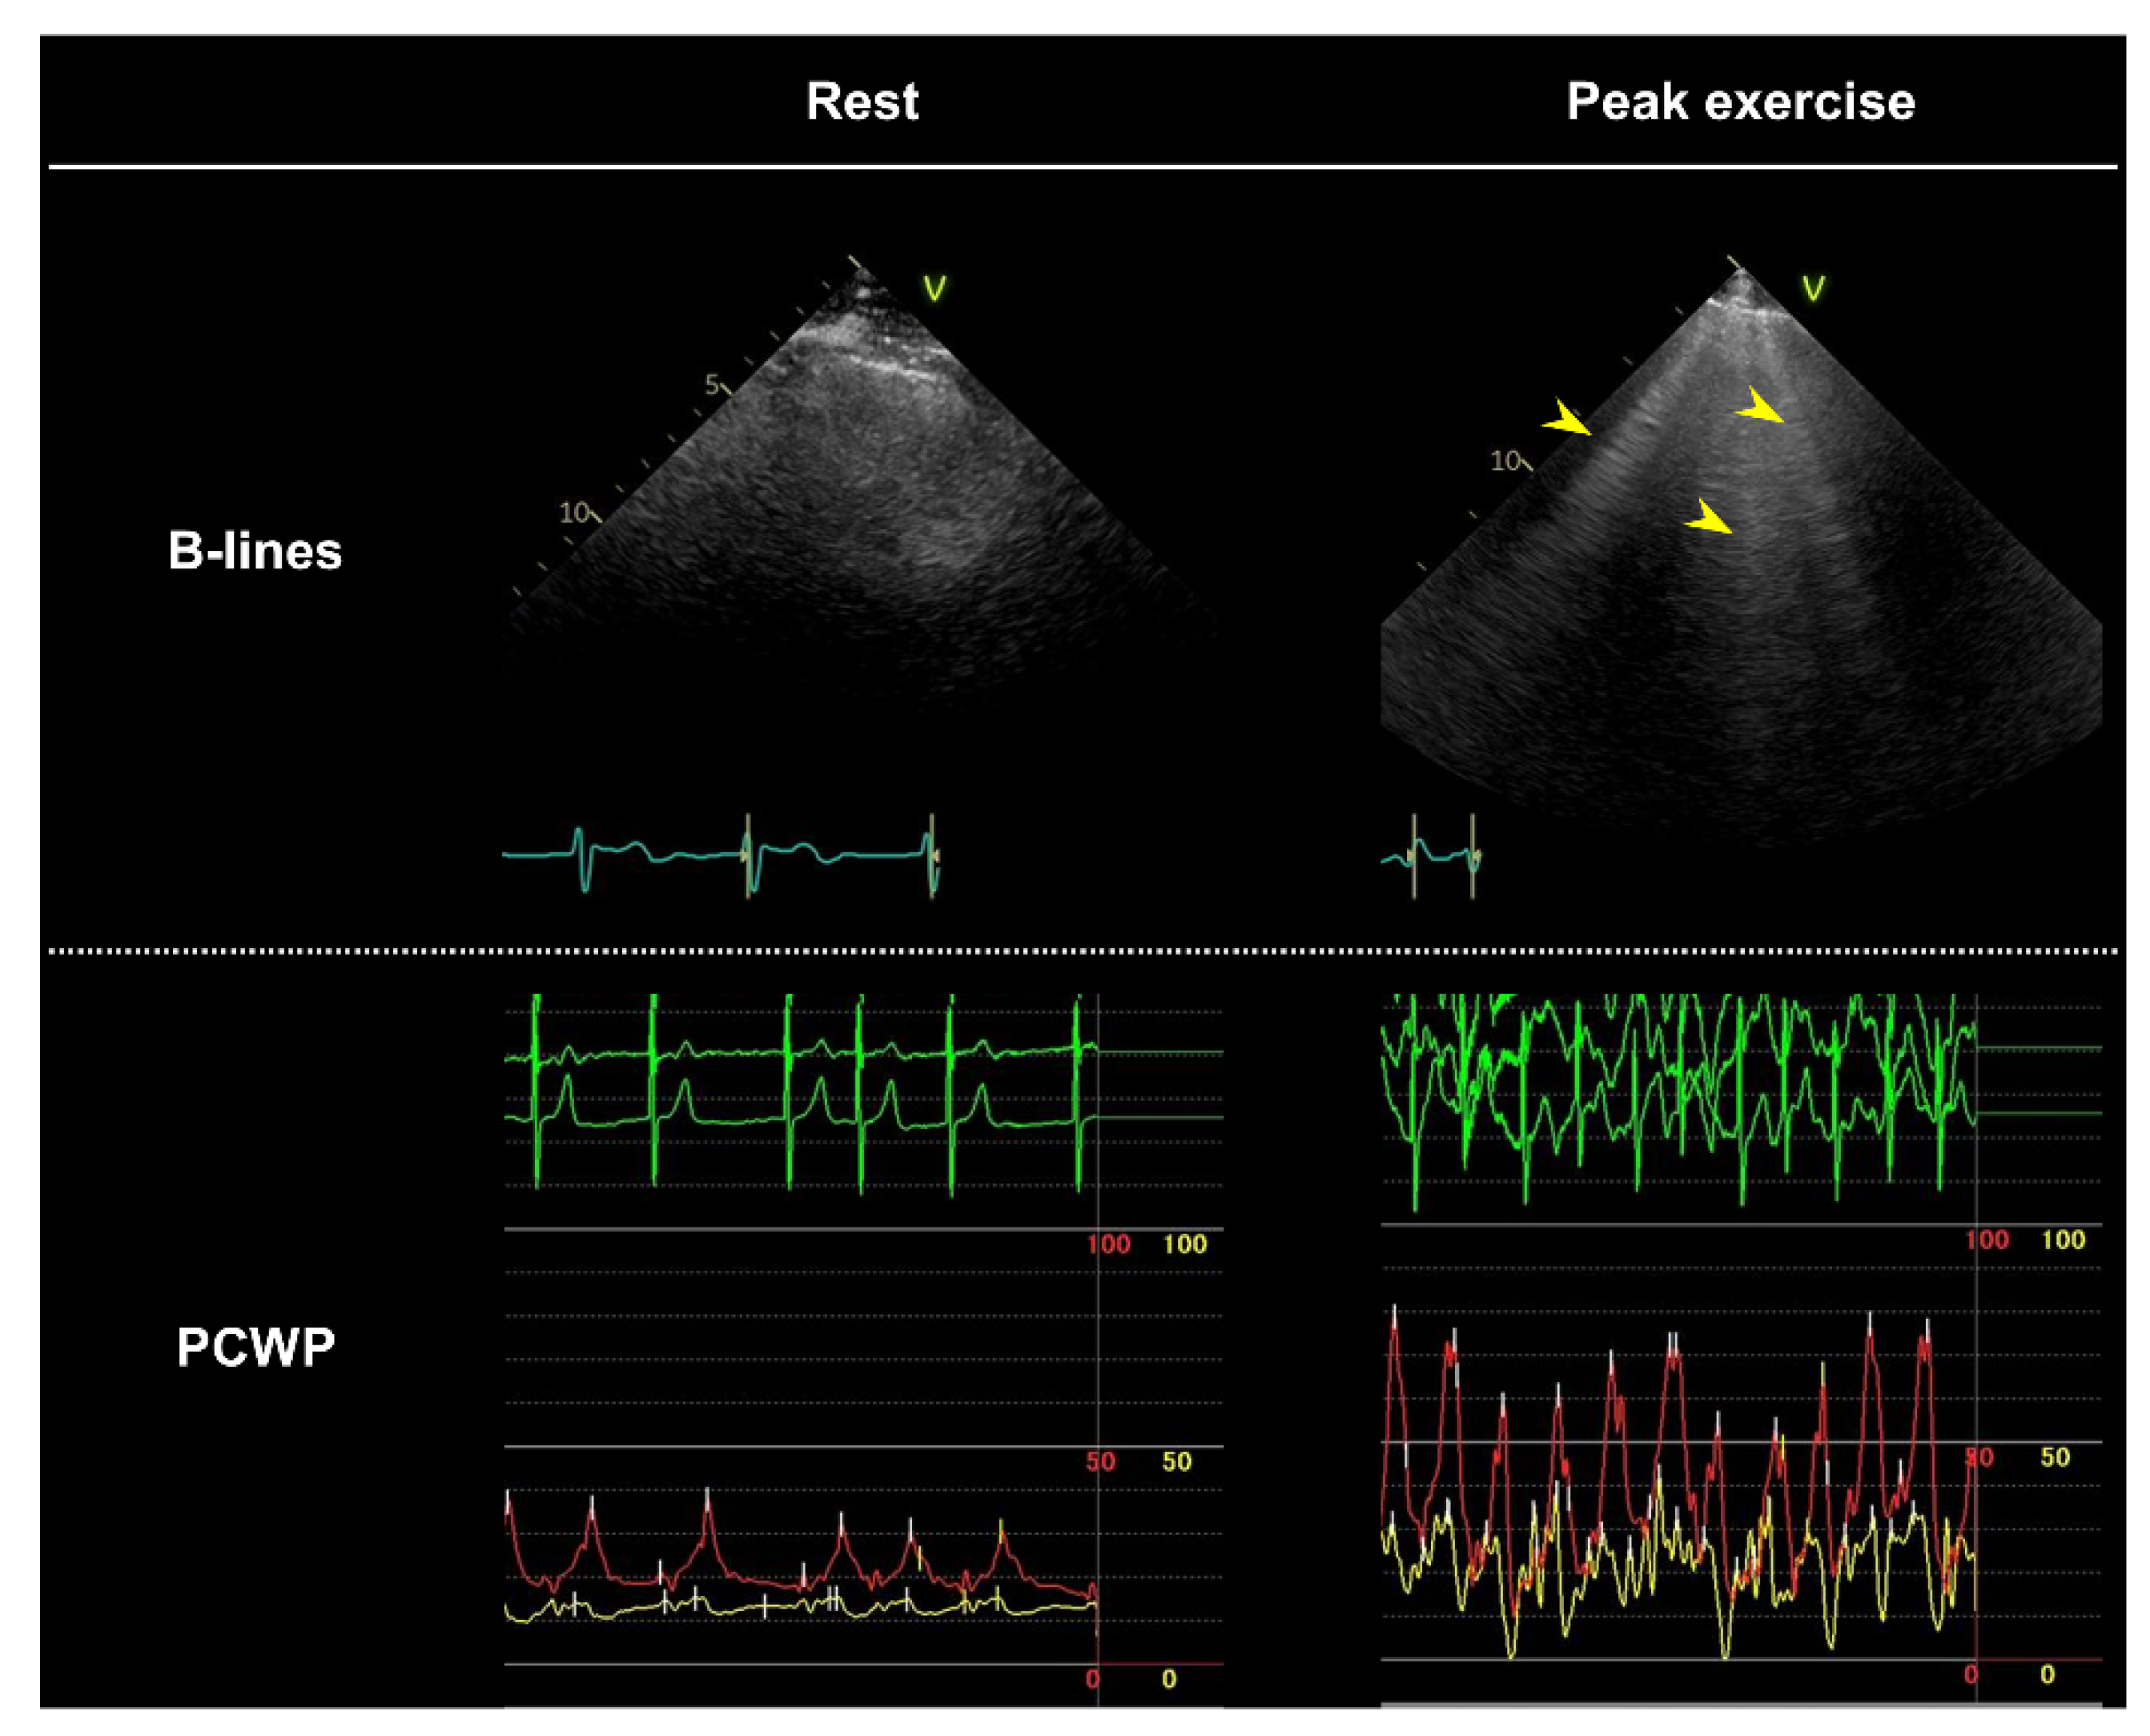

| What is the diagnostic value of other candidate markers of congestion during diastolic stress echocardiography, such as echocardiographic B-lines or left atrial strain [85]? | The presence of multiple B-lines may be useful in detecting pulmonary congestion that develops during exercise [63]; however, it is unclear how the data should be interpreted (e.g., the optimal cutoff value for B-lines is unknown). Further studies are warranted to establish the optimal role of the assessment of B-lines in diastolic stress echocardiography. |